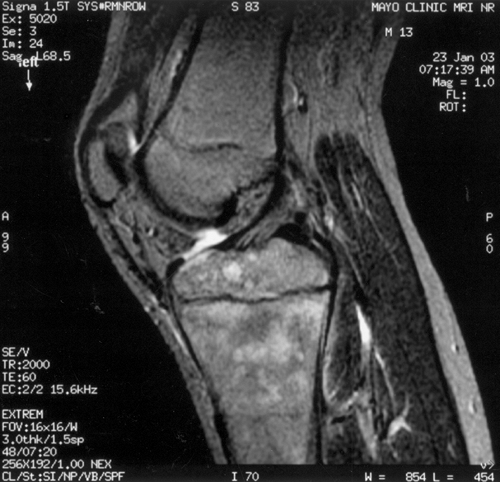

![]() |

Figure 13.4

A 5-year-old child presents with an increasing limp over 48 hours and with suspected musculoskeletal infection. History and physical examination do not localize the process. Erythrocyte sedimentation rate (ESR) and C-reactive protein (CRP) are elevated. A: The lateral (as well as the anteroposterior) radiograph of the spine is normal. B: Technetium bone scan shows increased isotope uptake in the L4 and L5 vertebral bodies suggestive of discitis, but neoplasm cannot be excluded. C: T2-weighted MRI helps confirm the diagnosis of discitis, demonstrating that the process is centered in the L4-L5 disc with no evidence of neoplasm, bone, soft tissue, or epidural abscess. Intravenous followed by oral antibiotic treatment was initiated, with complete resolution of symptoms after a total antibiotic therapy duration of 3 weeks. D: Final follow-up 3 years later demonstrates a normal lumbar spine radiograph in the asymptomatic patient. |